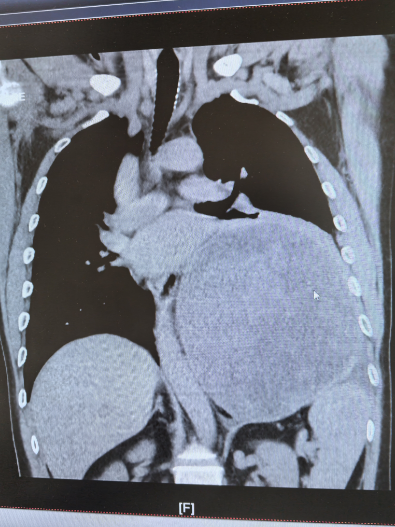

近日,北京天坛医院胸外科团队在多学科协作下,历经4小时,成功为患者完整切除左侧胸腔内直径近19厘米的巨大神经鞘瘤。此次手术的顺利完成,不仅彰显了北京天坛医院胸外科的精湛技术,更体现了多学科协作在疑难重症救治中的关键作用。

为寻求一线生机,杜先生通过熟人介绍并结合网上查询,慕名找到北京天坛医院胸外科主任医师杨增。医院胸CT检查结果令人揪心,成年人一侧胸腔宽度大约10-15厘米,而杜某的肿瘤直径近19厘米,占据了左侧多半个胸腔,把心脏和主动脉都挤偏了,原本竖直的主动脉已经弯到了右侧。再继续发展,一旦压迫到降主动脉,就会引发急性心衰,随时可能猝死。但更棘手的是,如果进行手术,该肿瘤为实性肿瘤,无任何囊变,血运极其丰富,且与左肺下叶致密粘连,甚至可能累及脊髓,手术中稍有不慎就可能导致心脏骤停、心律失常、大出血、截瘫等严重并发症。“不能因为风险高就放弃患者。”杨增了解情况后,当即决定将患者收入院。